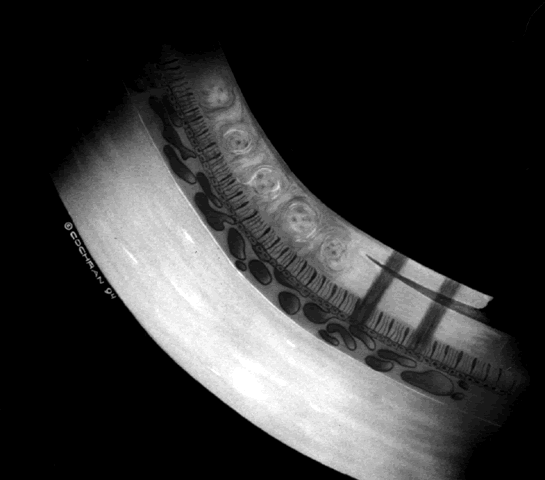

ROP accounts for a large number of retinal detachments in the pediatric

population. The International Classification of Retinopathy of Prematurity

helped greatly to improve communication about, and consequently

treatment of, ROP. It describes affected eyes in terms of stage, zone, and

absence or presence of plus disease18 (Figs. 1, 2, and 3). Screening of premature infants is an important feature in the care of

ROP, which is perhaps the most significant and enduring finding of the

Cryotherapy for Retinopathy of Prematurity Study (Cryo-ROP Study).19

Although several screening protocols have been suggested, we have found that children whose birth weight was 1500 g or less should be screened initially at 4 to 6 weeks after birth, and then every 2 weeks until they reach retinal vascular maturity, which is when nasal vessels in the horizontal meridian have grown to within 1 disc diameter of the ora serrata. During that time, if a child shows threshold disease as defined by the Cryo-ROP Study, namely five clock-hours of contiguous or eight clock-hours of discontiguous neovascularization (stage 3 ROP with plus disease), it is recommended that the child have peripheral ablation with either cryotherapy or laser treatment.19 Newer studies have suggested that zone 1 children may require earlier peripheral ablation.20 The child who fails to respond to peripheral ablation may require further surgical intervention. Two large series reported that scleral buckling for stages 4A and 4B retinal detachments resulted in a retinal reattachment rate of approximately 70%.21,22 These studies were both retrospective; however, they did show a strong trend toward a higher reattachment rate with scleral buckling than the natural history of these detachments, which have a 55% chance of progression of retinal detachment from stage 4 to stage 5 ROP.23 When first assessing a child's retinal detachment, one must judge the amount of effusive versus tractional detachment (Figs. 4 and 5). Scleral buckling would be considered for the child who shows a predominately effusive stage 4B detachment as opposed to a stage 4 predominately tractional detachment, for which lens-sparing vitrectomy may be recommended.24 For a child who has a great deal of retrolenticular touch, lensectomy/ vitrectomy and membrane peeling would be recommended. It appears that the “window” for lens-sparing vitrectomy may be rather brief. In one series, the postconceptual age of the lens-sparing vitrectomized eyes was 42.6 weeks, as opposed to 46.9 weeks for eyes that needed lensectomy/vitrectomy and membrane peeling. This small time difference in the postconceptual age shows the often rapid evolution of this detachment from one in which the lens is salvageable to one in which the lens is unsalvageable. This highlights the need for timely screening of eyes, identification of eyes with progressive disease, and rapid intervention.25